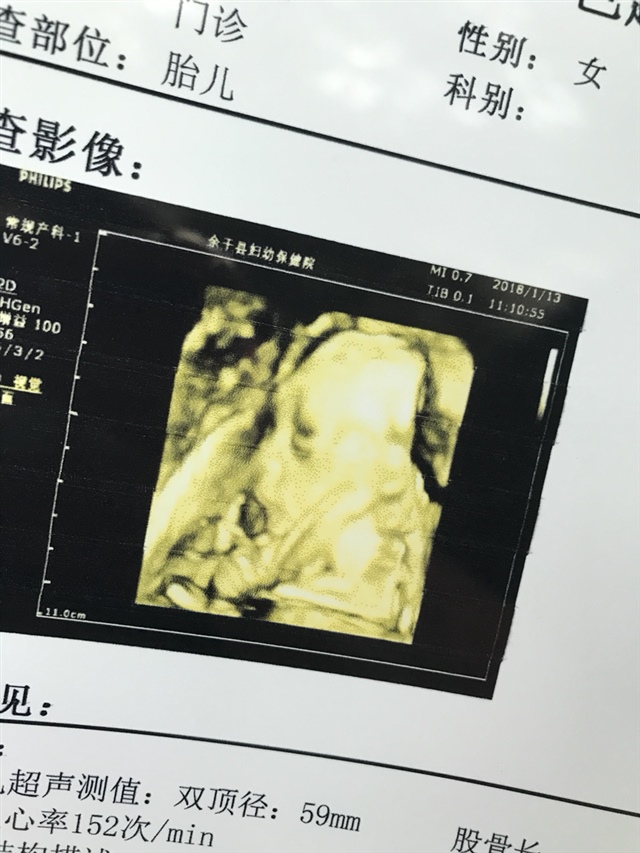

孕14周+6天

正在吐舌头做鬼脸吧